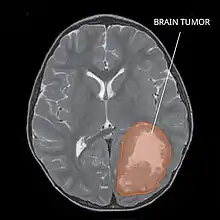

| Primitive neuroectodermal tumor of the central nervous system in a 5-year-old |

PNET has five subtypes of tumors: neuroblastoma, ganglioneuroblastoma, medulloepithelioma, ependymoblastoma, and not otherwise specified PNET.[1] It is similar to medulloblastoma regarding histology but different regarding genetic factors and tumor site. It is a rare disease occurring mostly among children,[1][2] accounting for 1.9 to 7% of childhood brain tumors.[2] Symptoms involve emotional, visual, motor, and speech defects.[2] Magnetic resonance imaging (MRI) and computed tomography (CT) are used to diagnose PNETs.[2] Even though a universal treatment plan hasn't been stablished yet, common strategies involve chemotherapy and radiotherapy for individuals older than 3 years of age.[1][2] Their efficacy, however, is still controversial.[2] Surgery can be used to remove mass affected by tumorous cells.[2] The prognosis of the disease is more positive for adults than for children, who have a higher probability of having sequelae from the tumor.[1][2]